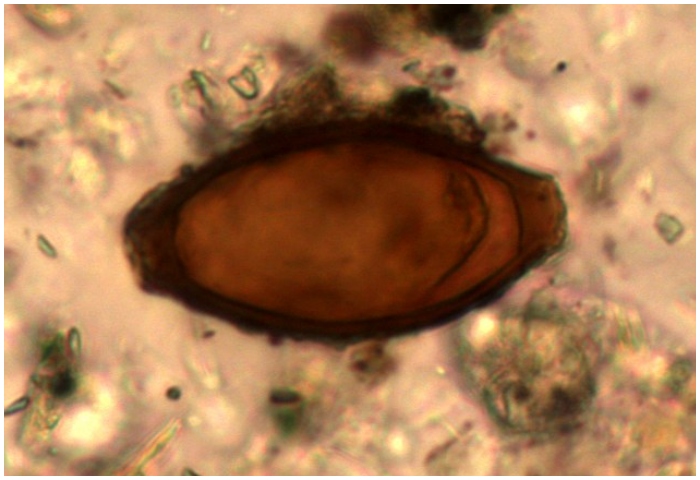

Parasitic Worms

In the Viking Age, parasitic worms were a common affliction, primarily attributed to consuming raw or undercooked meat and less-than-ideal hygiene practices. The Vikings’ dietary habits, including a fondness for organ meats, increased their exposure to these parasites.

ADVERTISEMENT

futurity

Despite the era’s reputation for cleanliness relative to contemporaries, the limitations of their hygiene practices could not fully prevent such infections, highlighting the everyday health challenges in Viking society.